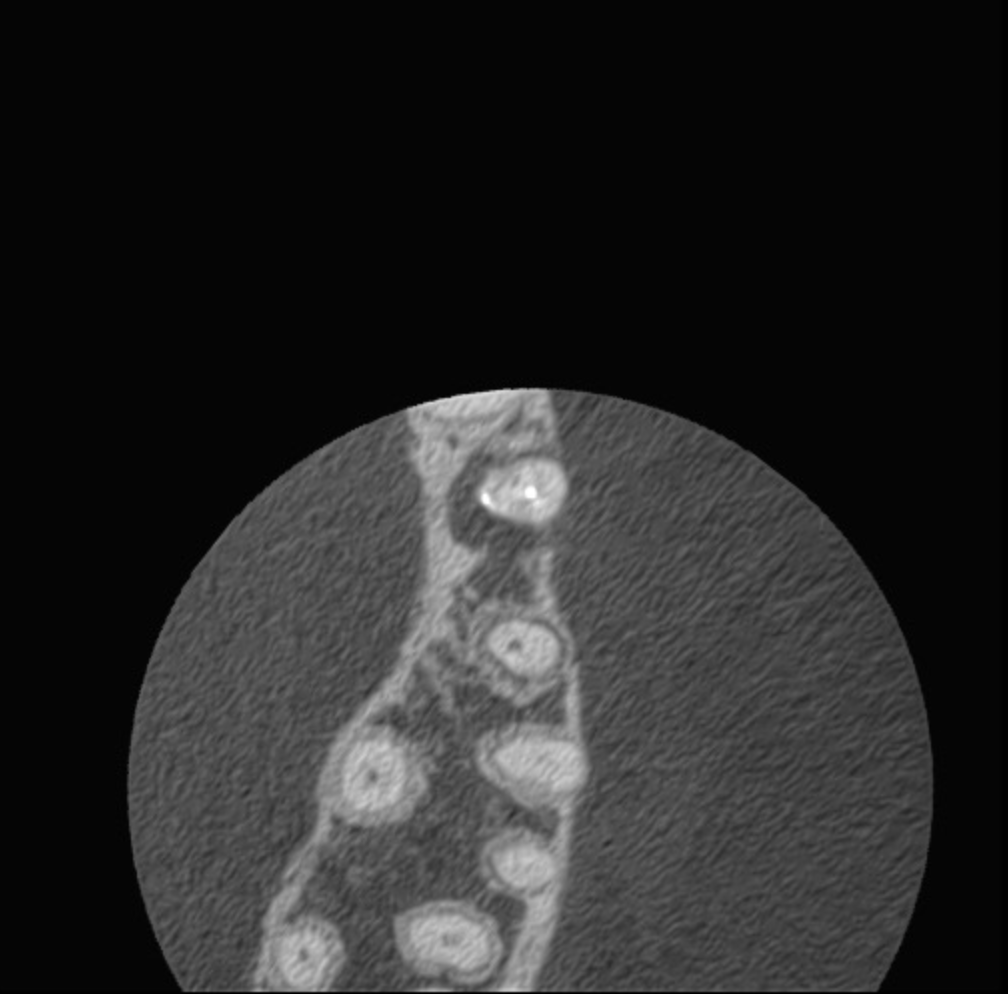

Casos de anatomia compleja

Bifurcación conducto palatino apical

Molar gran curvatura bifurcación palatino

Molar superior anatomía compleja